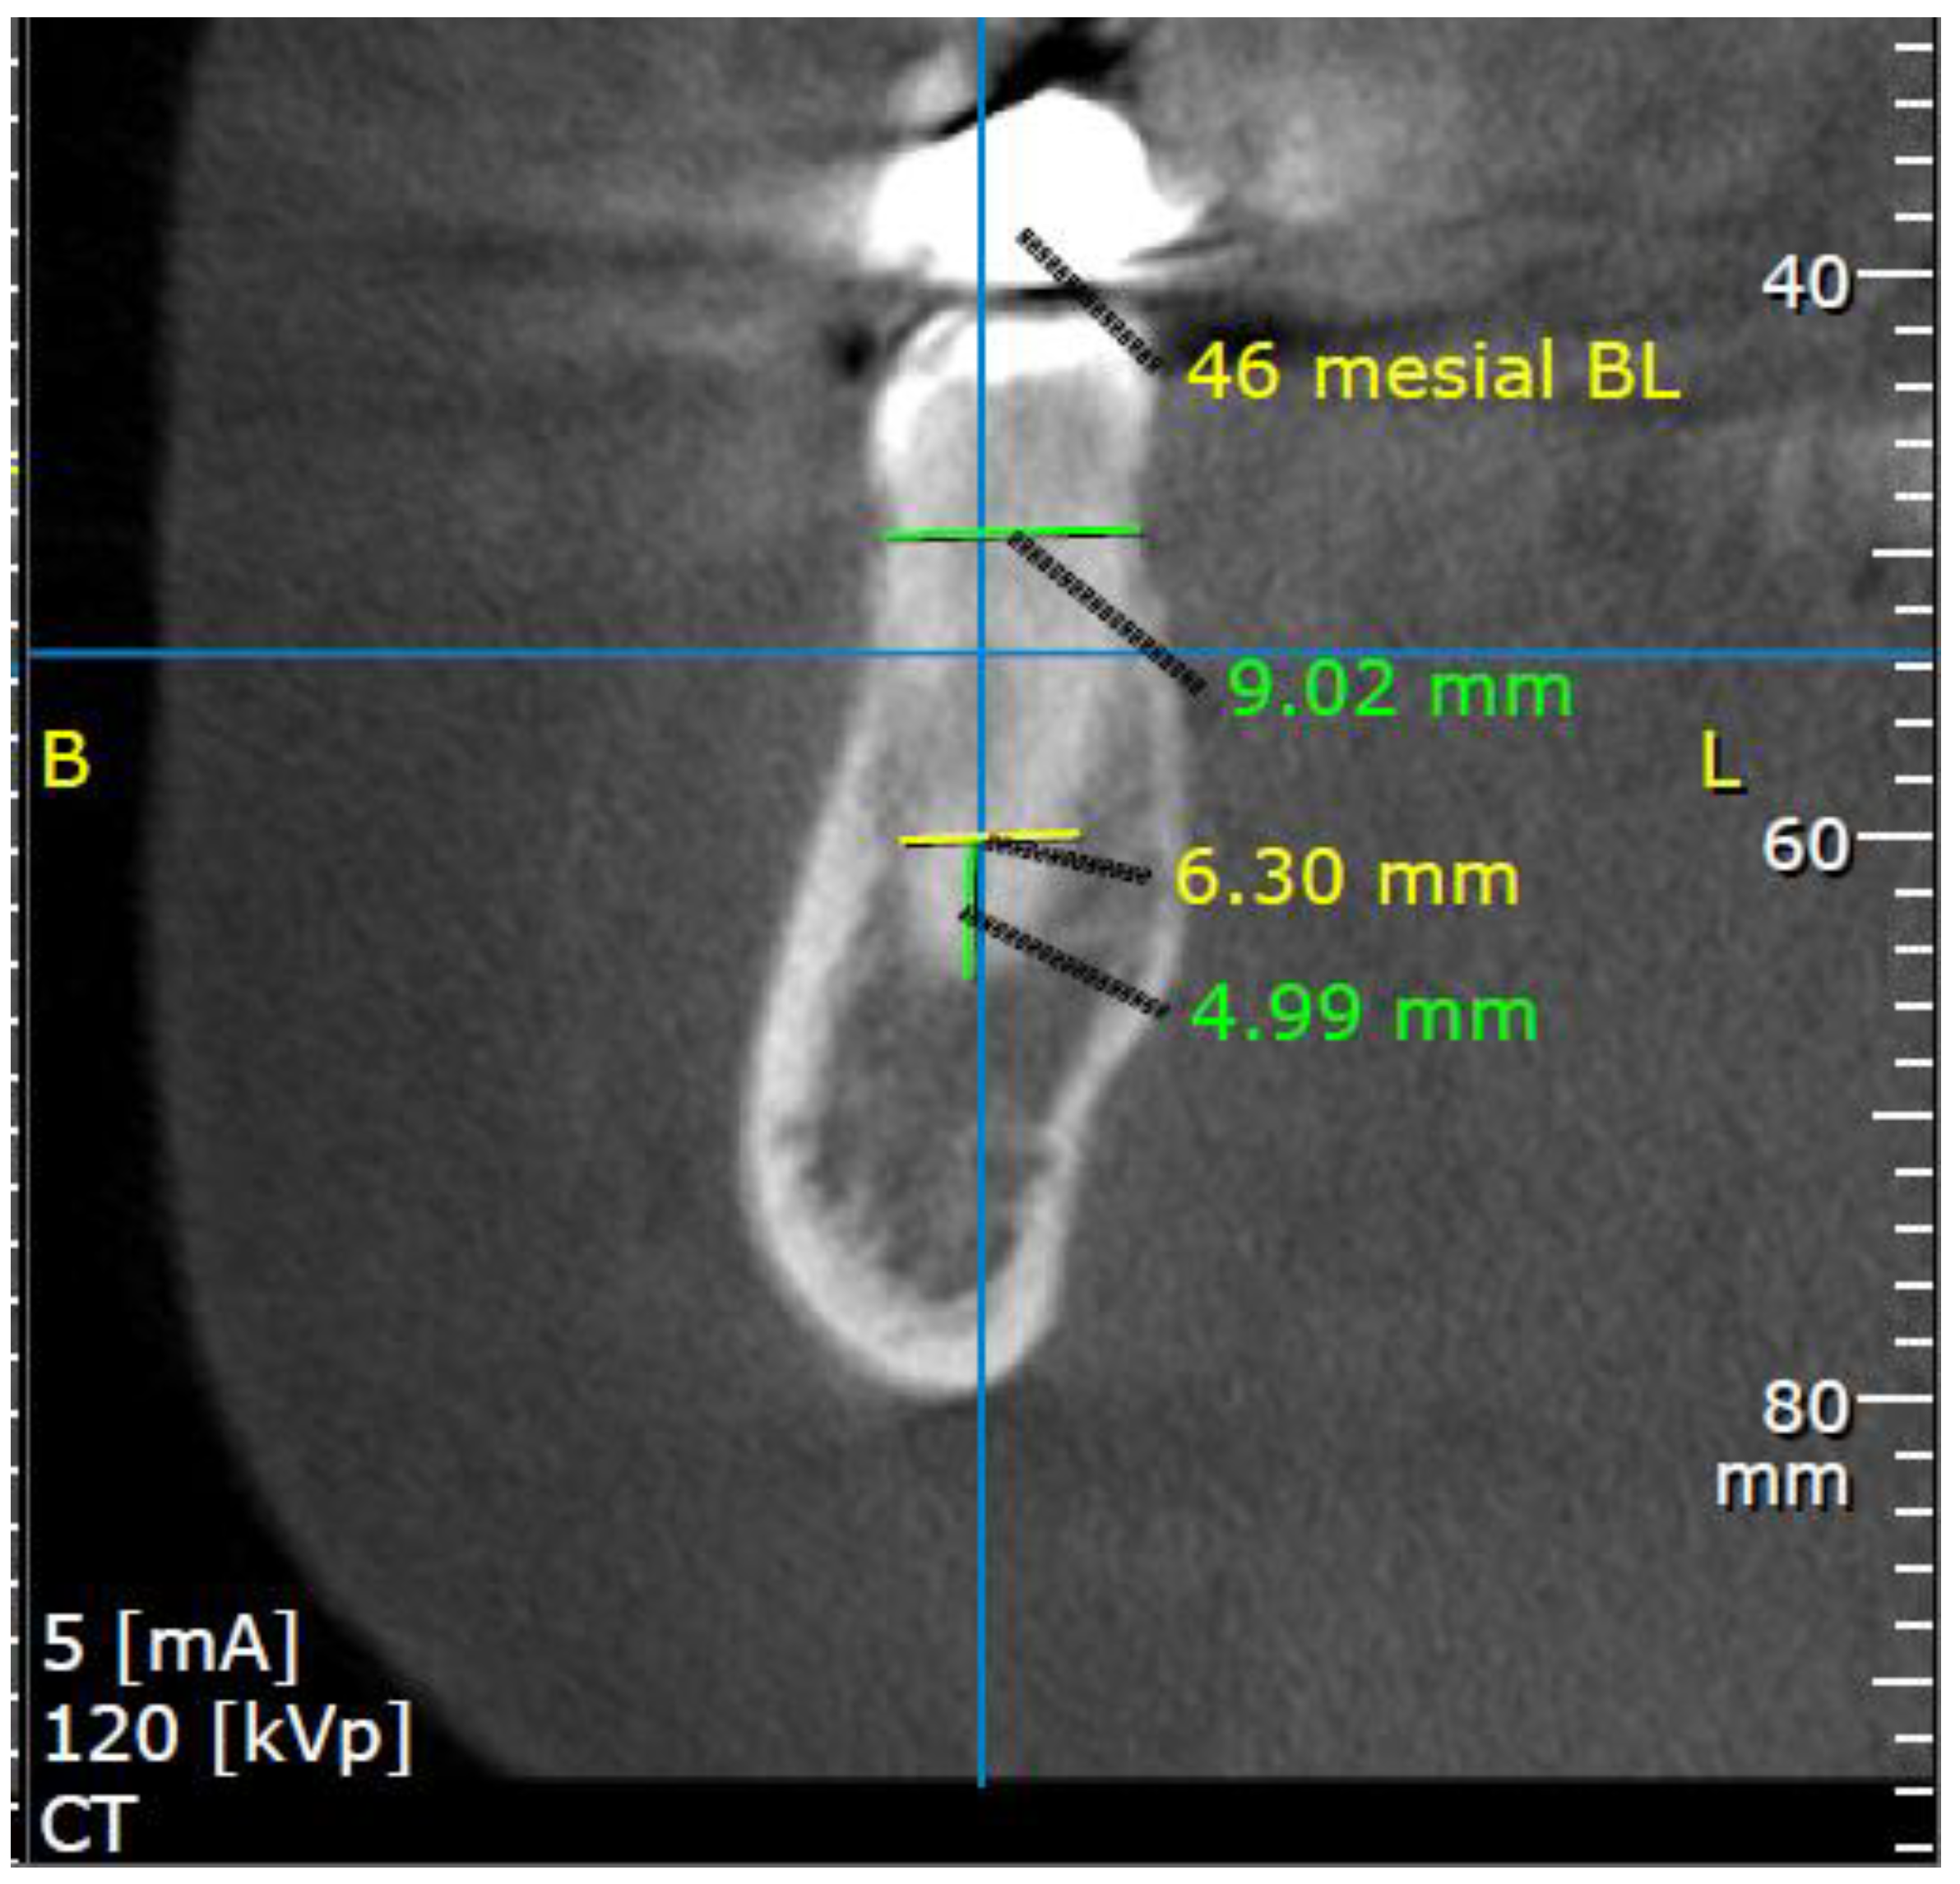

2.3. Measurements

3.2.3. Buccolingual Aspect